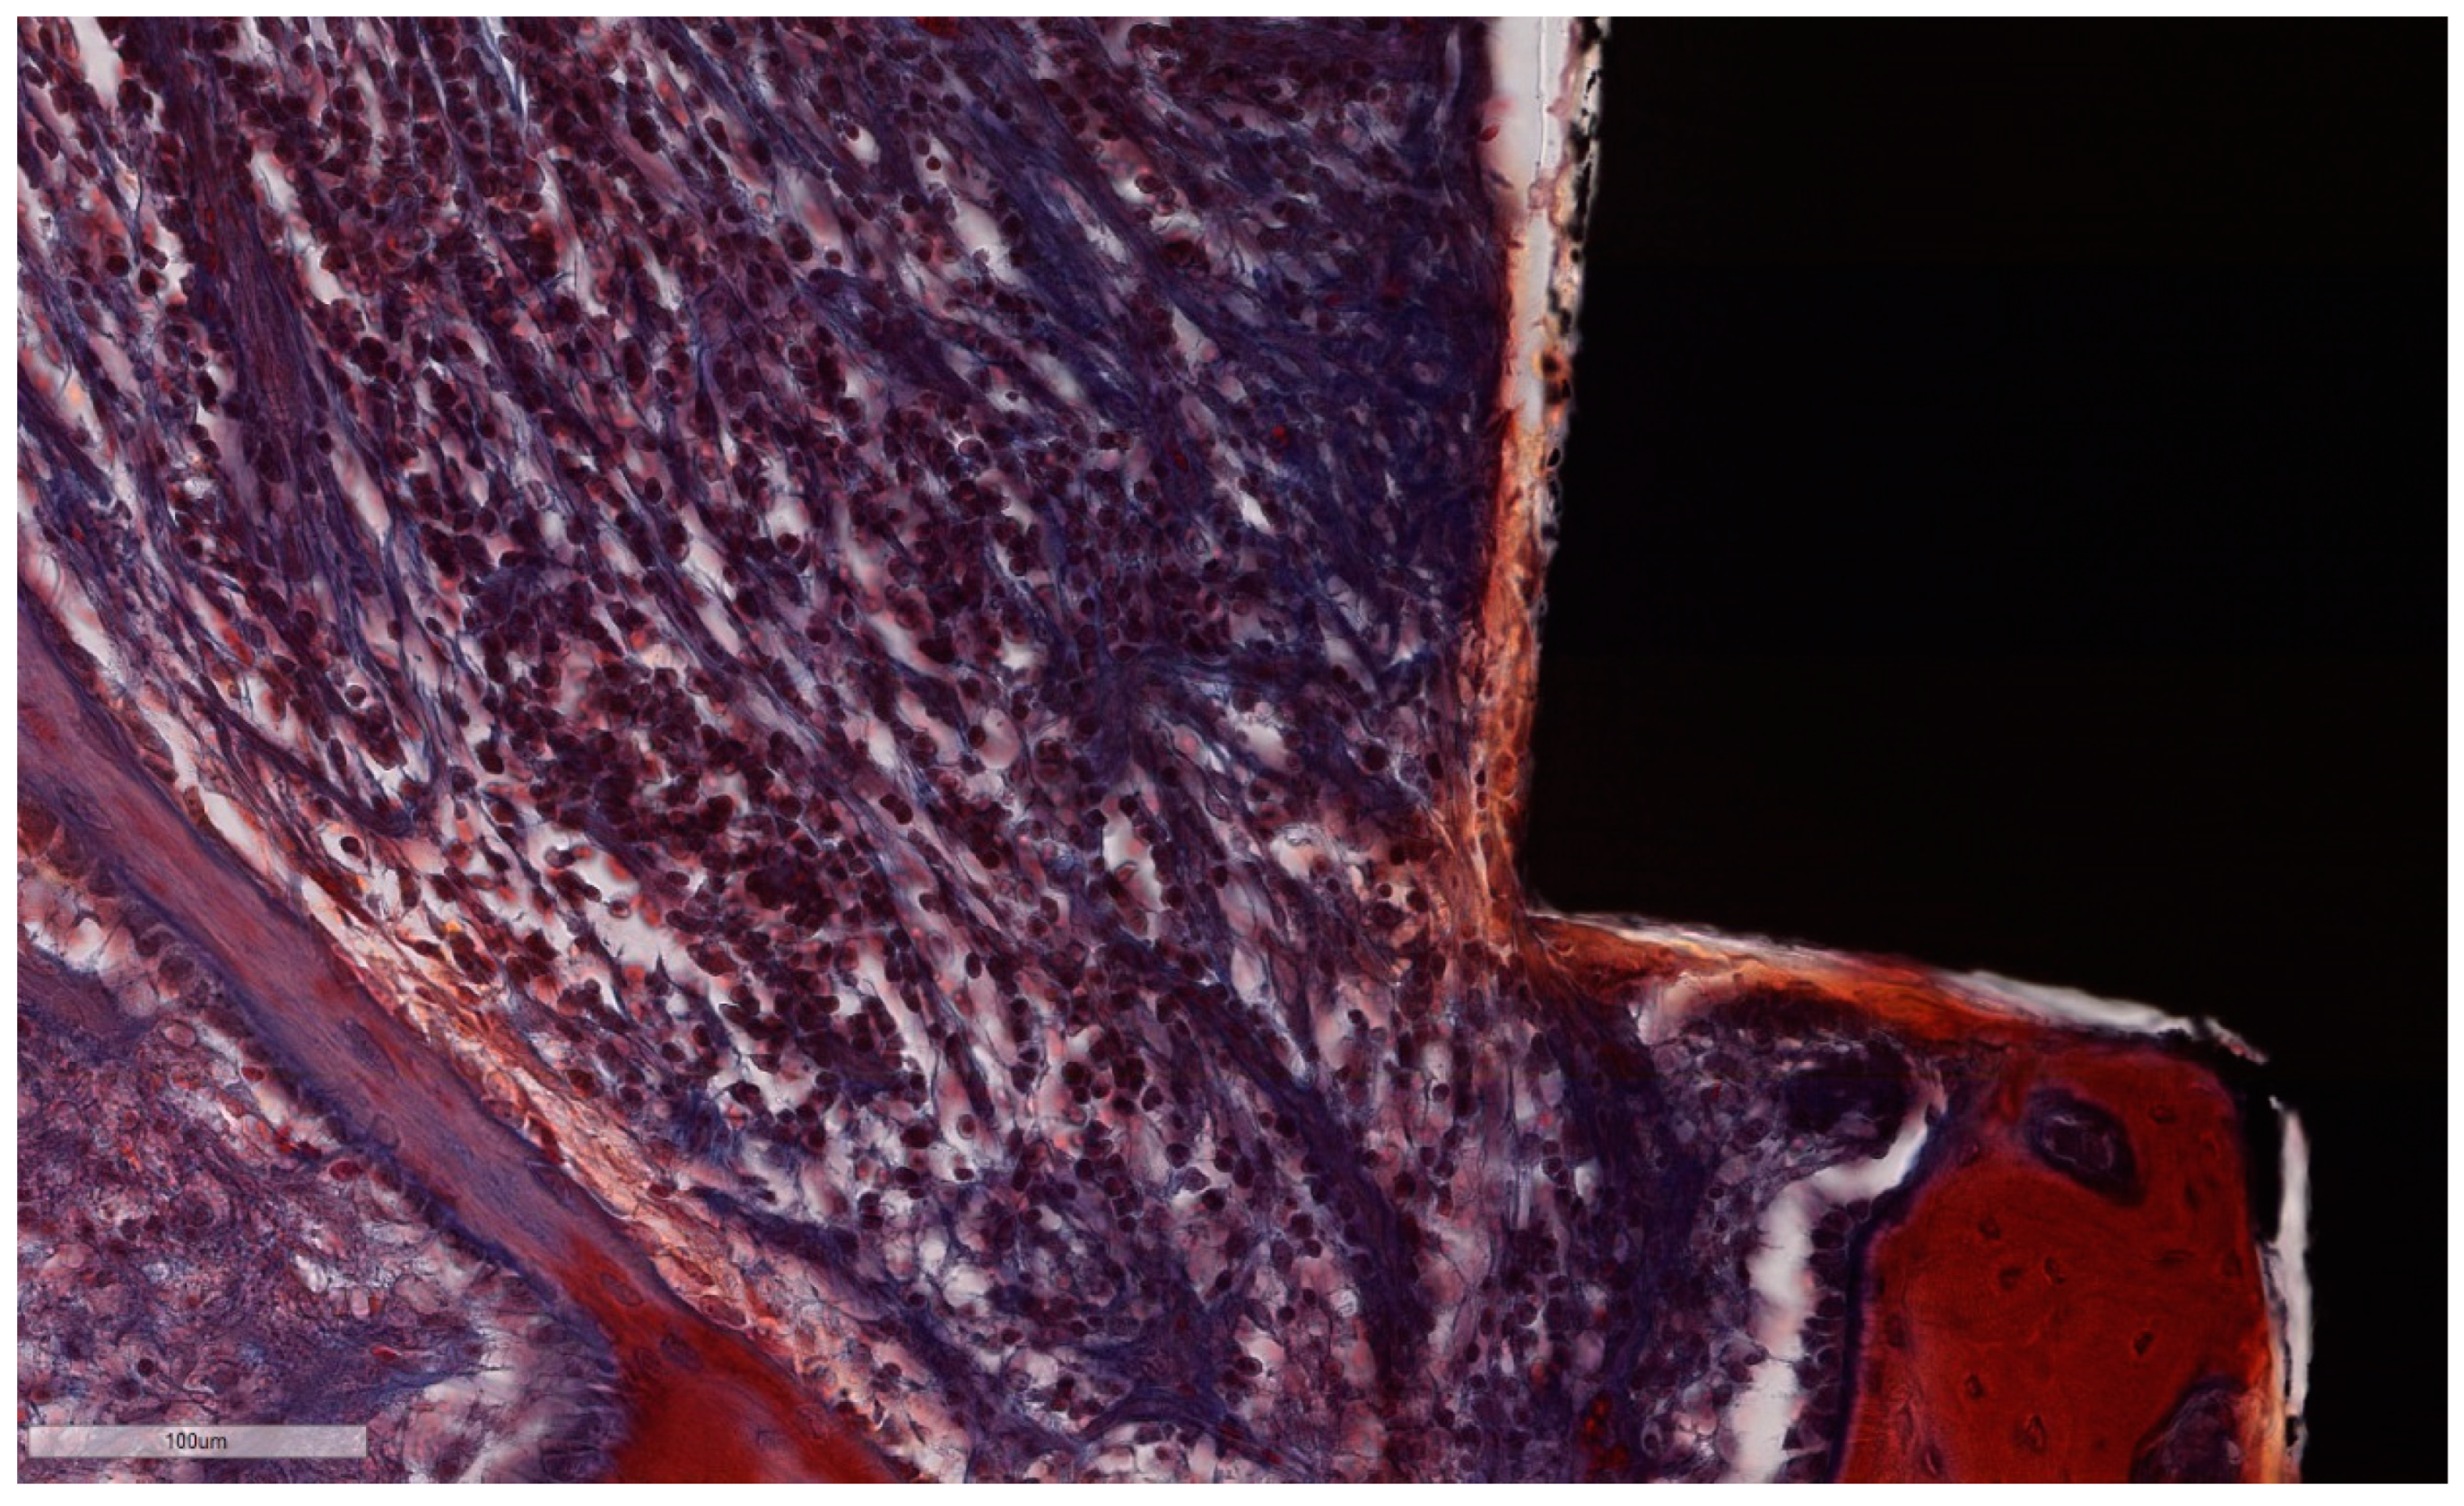

Figure 13. ICT in direct contact with the implant surface, without an interposed epithelial lining. Note the abundant lympho-plasmocytic infiltrate, which progresses inside the bone marrow, the thin bone trabeculae left after remodeling along with prominent osteoblast rim (implant #3, MGA, bar measure is 100 µm).